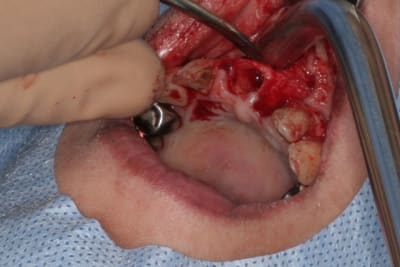

12/06/2014 à 13h50

Purée, tu prends des risques énormes en fourrant ton bio oss puis en vissant les implants dans la masse de bio oss, de un, et sans membraner l'interface pilier implant, de deux...

Je suis peut-être vieux jeu mais c'est, à mon avis, dangereux d'un point de vue bactériologique.

c'est pas la première fois que je fais çà...;-)

et çà me donne plutôt de bons résultats

après tout...le périoste n'est-il pas la meilleure membrane?

par contre il faut veiller à avoir une bonne étanchéité au niveau des sutures...